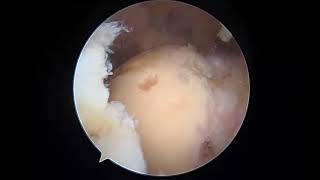

Repair Of A Partial-Thickness Rotator Cuff Tear...

609

6:18